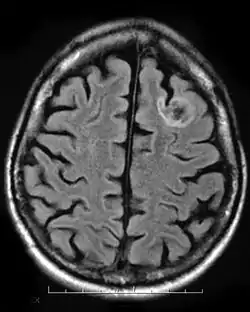

La imagen por resonancia magnética (MRI, MRI) o tomografía computarizada (TC) muestra lesiones en la corteza cerebral. Las lesiones se extienden en todo el espesor de la corteza. En la TC se puede ver densas lesiones de la corteza con discapacidad (hipodensa) bien delimitadas . Los quistes se encuentran a menudo calcificados. Una acumulación de medio de contraste no es típica. Un desplazamiento del tejido circundante no se produce. A veces hay una deformidad del cráneo sobre el tumor. En la RM, las lesiones aparecen bien definidas, no invasoras, y sin edema perifocal (captación de líquido en el parénquima cerebral circundante). Como es típico, la configuración multinodular (que consta de muchos como estructuras nodulares) se ha descrito.[1][7]